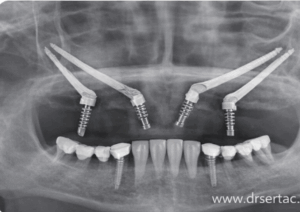

Aynı gün implant, implantın yerleştirildiği gün üzerine geçici dişin takılması işlemidir. Böylece hasta dişsiz kalmadan tedavi sürecini tamamlar.

Aynı gün implant, uygun hastalarda hızlı ve etkili bir çözümdür. Ancak doğru planlama ve uzman değerlendirmesi gerektirir.